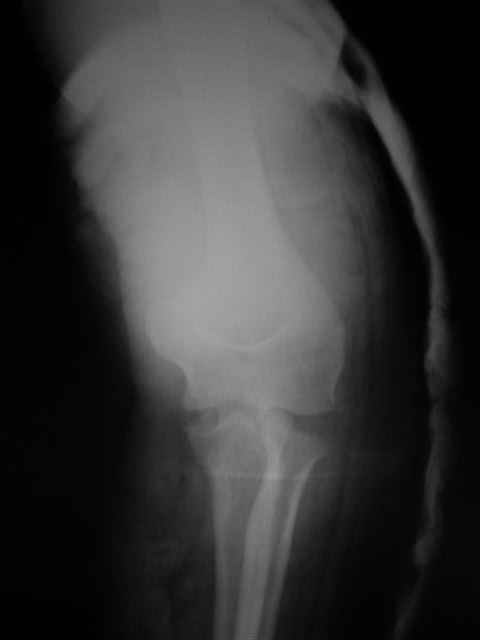

Вывих костей предплечья и перелом головки лучевой кости. |

Уважаемые коллеги!Помогите с источниками литературы по вопросу о сроках резекции головки лучевой кости и гетеротопической оссификации после вывиха костей предплечья. Необходимо ответить на жалобу, где больная просит возместитьматериальные затраты на лечения с лечащих врачей, которые участвовали влечении с 4.09.04 по 10.11.04, объясняет, что врачи нарушили стандарты леченияи поздно направили на оперативное лечение.История болезни, женщина 46 лет упала дома 4.09.04, получила заднелатеральныйвывих костей предплечья и перелом головки лучевой кости, под местной анестезиейвывих вправлен, на контрольной рентгенограмме соотношение отломков головкилучевой кости расценено, как удовлетворительное. Наложена задняя гипсовая шина.Лечение: холод, кетанов 3 дня, магнитотерапия, ЛФК пальцев, рентген контрольчерез 7 дней, с 8.09.05 наклофен 50 мг 2 раза в день. 11.09.04 на контрольной рентгенограмме состояние отломков прежнее. 30.09.04. Гипсовая шина снята через 26 дней. Лечение: ЛФК, массаж, электрофорезлидазой.9.10.04. В левом локтевом суставе сгибание 80, разгибание 120.19.10.04. Сгибание 80, разгибание 140, ротационные движения в пределах 10 гр.28.10.04. Сгибание 80, разгибание 150, ротационные движения в пределах 10 гр.10.11.04. На рентгенограмме локтевого сустава отмечается гетеротопическаяоссификация.Учитывая неэффективность консервативного лечения, больная направлена на оперативноелечение.Больная по собственным каналам уехала в г. Киев, где произведенарезекция головки лучевой кости, после операции развился неврит лучевого нерва.На данный момент больная продолжает лечение у нейрохирурга.-- С уважением,Анатолий Борзунов

Mozgounov> А есть снимки?

Во время встречи фотоаппарата не было, забрать снимки на время, муж больной снимки не разрешил.